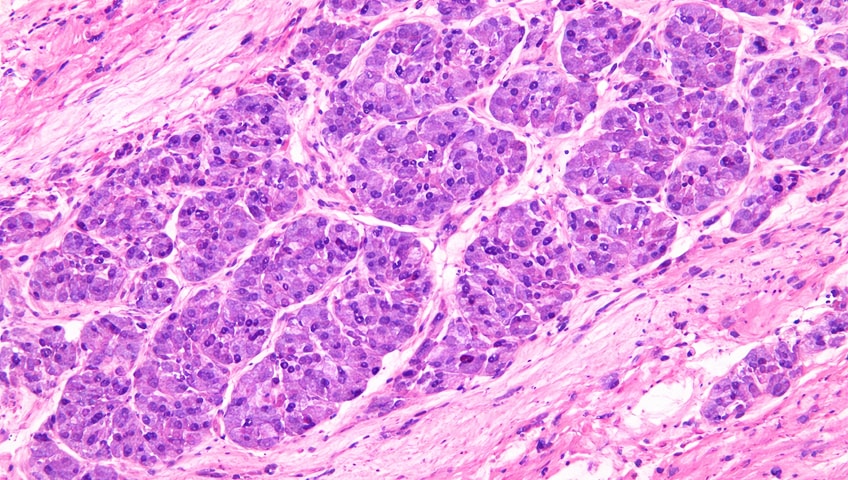

Our science is validated sufficiently, and we have clinical proof that Leukocyte-Tells (SL-28) works. Here is IRL imagery to show it.

Leukocyte-Tells (SL-28)

result in tumor destruction

SL-28 is a different kind of immune cell adoptive therapy, and unlike CAR T or TILs, has proven to be effective in treating a broad range of advanced solid tumor cancers, even in cases with a heavy tumor burden.

Second Life Therapeutics has developed Leukocyte-Tells (SL-28), a universal cell therapy designed to treat a broad range of advanced solid tumors.